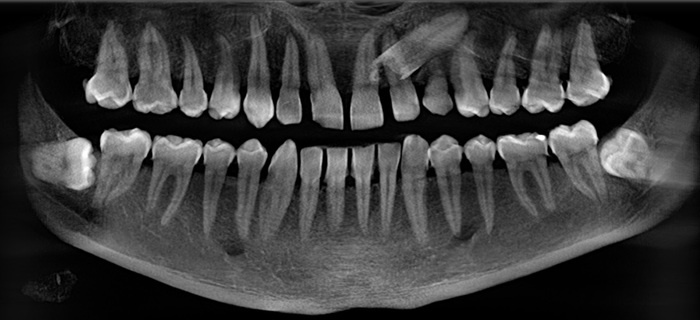

Ретенированный клык. Тот еще адок. Ортодонты при помощи брекетов и специальных тяг стараются такие зубы ставить на место, но это удается не так часто. Стоит заметить, что расположение подобных зубов в челюсти – непредсказуемо. Бывают случаи, когда лучше туда и не лезть.

В основном, зная про наличие такого зуба, необходимо периодически делать рентгеновские снимки и наблюдать не творит ли он бардак.

В случае, о котором я расскажу сегодня произошло следующее. У пациента 50ти лет вдруг ломается молочный клык. Вы не ослышались, молочный клык в 50 лет. Если постоянный зуб не прорезается или вдруг отсутствует его зачаток, то, условно, у молочных зубов не происходит полноценный процесс рассасывания корня, такие зубы могут служить долгие годы.

Плюс перспектива остаться вовсе без зуба пациента, мягко говоря, не привлекала. Проблема была лишь в том, что где-то там внутри сидел клык. Его наличие не позволяет поставить имплантат нужных размеров, не задев этот зуб.

Рентгеновский снимок после установки постоянной коронки: